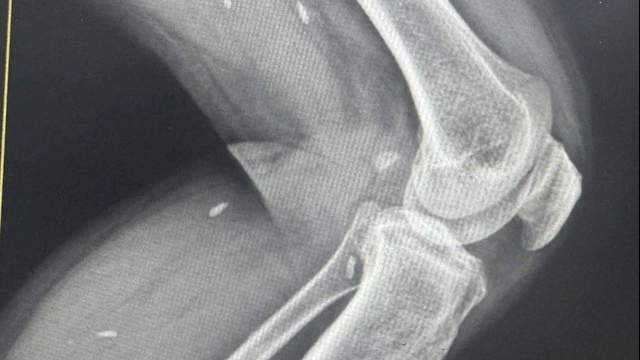

Theo Trưởng khoa cấp cứu Bệnh viện Nhi Đồng 2, hai bệnh nhi nhập viện trong giờ thứ 5 của bệnh (khoảng 21h) trong tình trạng tổn thương đa cơ quan, hai trẻ quấy, kích thích, cử động tay chân, mạch bắt nhẹ, hỗ trợ thở bằng bóp bóng, chấn thương hai mắt, tổn thương nhãn cầu, rách giác mạc, không khảo sát được đồng tử, bụng mềm, ấn đau, vết thương vùng cổ có rò khí, rách gan, rách ruột... khiến bệnh nhi rơi vào tình trạng nguy kịch.

“Hai bệnh nhi nhanh chóng được cấp cứu, hội chuẩn liên chuyên khoa, hội chẩn toàn viện và tiến hành truyền dịch chống sốc, trợ tim, vận mạch, kháng sinh phổ rộng... Ngay sau đó, 2 em đã được phẫu thuật thám sát. Ca mổ kéo dài 11 tiếng để lấy các dị vật ở vùng mắt, bụng, phổi... và khâu liền giác mạc, khí quản, ruột, cắt lọc da hoại tử cho bệnh nhi”, BS.CK2 Phạm Thái Sơn, Trưởng khoa Hồi sức tích cực và Chống độc Bệnh viện Nhi Đồng 2 TPHCM cho biết.

Hiện cả 2 bệnh nhi đã qua cơn nguy kịch, tỉnh táo, có thể trả lời được. Tuy nhiên, 2 trẻ tiên lượng nặng, có khả năng thời gian tiếp theo các bệnh nhi sẽ phải thực hiện thêm các cuộc phẫu thuật khác để lấy hết các mảnh vỡ còn lại. Thời gian sau bệnh nhi có khả năng chịu nhiều di chứng, ảnh hưởng thị lực, khả năng nhiễm trùng nặng cao...